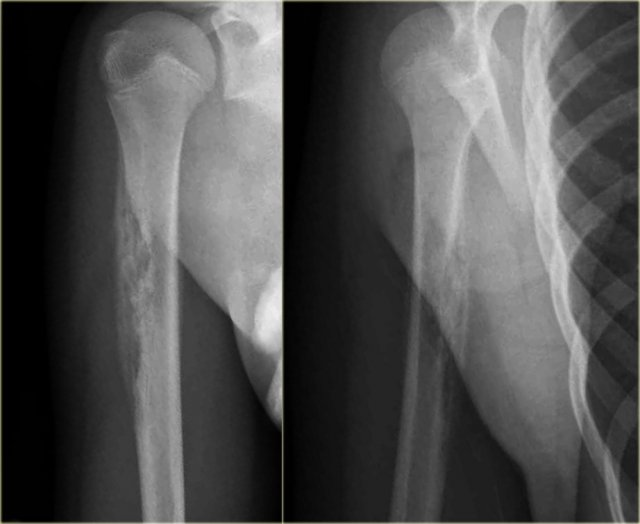

Here images of a 30-year-old male.

There is a wel-defined lytic lesion of the olecranon with several ridges and a pathologic fracture.

The differential diagnosis includes giant cell tumor and ABC.

The T2WI+FS shows fluid-levels due to sedimentation making ABC the most likely diagnosis.

Biopsy however revealed Brown tumor.

Melorrheostosis of proximal humerus.